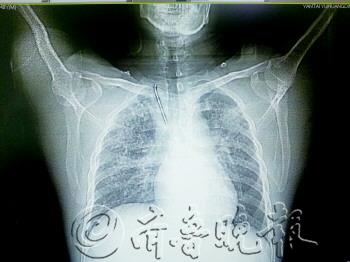

从CT片上能看到长长的钢钉。 本报记者 宋佳 摄

记者看到老曲的胸部CT,在他的右侧锁骨处有一根呈“7”形的金属物,长约7厘米,尖端直指心脏方向。“4年前丈夫被重物砸中右侧锁骨,致右侧锁骨骨折。”彭女士介绍,当时打进三根钢钉,两个月后到医院取钢钉时,有一根拔不出来,就一直留在了里面。

“当时医生说,留在体内也不会有影响,所以我们就没在意。”彭女士说,直到毓璜顶医院医生将CT片子展示给彭女士看时,她才回忆起这根被遗忘的钢钉。

对此,毓璜顶医院创伤骨科主任王新介绍,骨折受伤后这根钢钉虽然发生游走,但可以看出当初钢钉打入位置不正。但即使再难取,当时的医院也应想办法取出,否则留在体内时间过长,会发生移位。